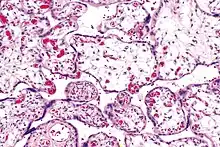

| Micrograph of villous immaturity. H&E stain. | |

Placental villous immaturity is chorionic villous development that is inappropriate for the gestational age.

Immature chorionic villi are larger and have more central blood vessels; thus, the diffusion distance for gas and nutrient exchange is larger and, therefore, placental function is impaired.

High mag.